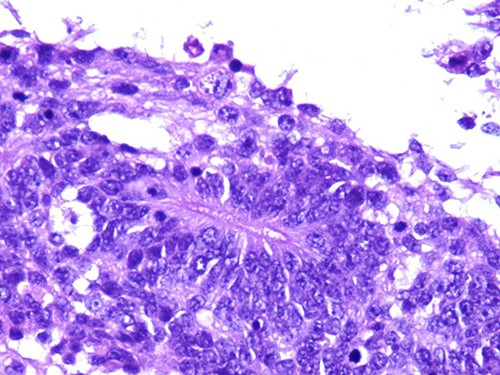

A 46-year-old woman, without clinical antecedent, presented with a tumor in the inner side of the left cheek which had rapidly grown for 3 weeks. Physical examination revealed an ulcerating mass measuring 4 × 3.5 cm, well-circumscribed, fleshly, with a white surface. There was submandibular lymphadenopathy, ranging in dimension from 1 to 1.5 cm in diameter. Magnetic resonance imaging (MRI) scan revealed the tumor of the cheek without mandibular bone infiltration or sinonasal involvement (Fig. 1). Chest computed tomography and abdominal ultrasound scan were unremarkable. An excisional biopsy was performed. Pathological examination showed a neoplastic proliferation composed of mixture of mature benign epithelial components, such as intestinal type, respiratory and squamous epithelia, and mature mesenchymal components, such as muscular tissue and cartilage (Fig. 2) and neuroglial tissue. In addition, immature and malignant tumor components were found such as small blue tumor cells resembling primitive neuroectodermal tumor (Fig. 3), adenocarcinoma and sarcoma with muscular and cartilaginous differentiation (Fig. 4). This tumor infiltrates the skeletal muscle with free margins. Immunohistochemically, epithelial components were positive for pankeratin; mesenchymal components showed desmin, myogenin and S-100 positivity and the primitive neuroectodermal tumor component was positive for NSE, CD99, GFAP, synaptophysin and focally for chromogranin. SALL4 was negative. The resected submandibular lymph nodes were devoid of malignant infiltrate. The diagnosis of TCS was established and the patient was treated by combined chemotherapy (cisplatine +5 fluorouracil) and radiation therapy. No recurrence was noted 6 months after treatment.

Photomicrograph of primitive neuroectodermal component with neural rosettes (magnification at ×400).